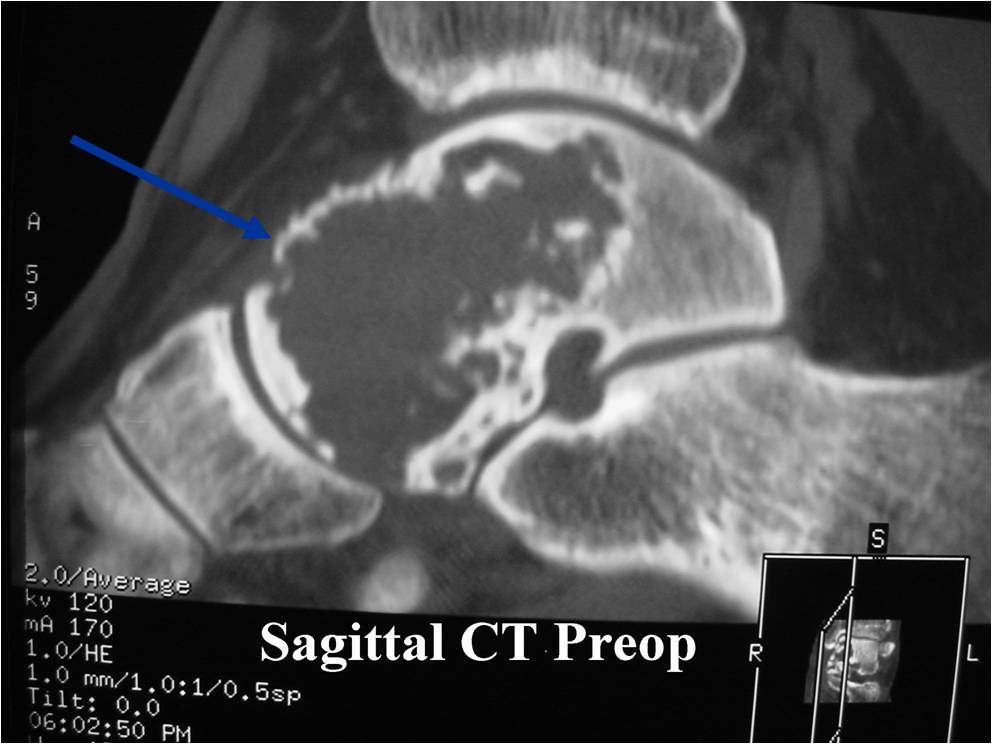

General Information Enchondroma is a benign indolent intramedullary hyaline cartilage neoplasm Accounts for 10% of all benign osseous tumors Limited growth, most lesions are less than 5 cm in maximal dimension Bones grow from a cartilaginous growth plate that...